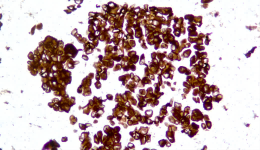

CLDN18.2 +++ 石蠟撈片標準品

Description CLDN18.2是Claudin蛋白質(zhì)家族的一員,位于細胞膜表面,Claudin18.2(CLDN18.2)表達具有特異性。其作為Claudins蛋白的一個(gè)亞型,在正常組織中僅表達于分化的胃黏膜上皮細胞。在胃癌、食管癌和胰腺癌等多種腫瘤中表達,并且不僅限于原發(fā)病灶,在轉移灶中也有表達。目前臨床研究中使用的檢測方法均為免疫組化。

IHC染色結果